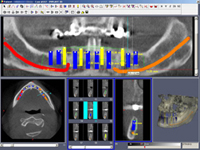

• Dokonalé vyšetření, stanovení diagnózy,naplánování ošetření - způsob, časový průběh,cena

Metoda All-on-four

Bezzubá čelist je hlavní indikací pro ošetření pomocí implantátů. Zejména celkové zubní náhrady v dolní čelisti mají velice nízkou stabilitu a držení díky velkému úbytku kosti.

S pomocí zubních implantátů můžeme díky různým kotevním systémům (třmeny, kulové hlavy, Locatory) zajistit stabilitu a držení protézy nebo při použití většího počtu implantátů zhotovit pevné náhrady – můstky nalepené nebo našroubované na pevno na implantáty.